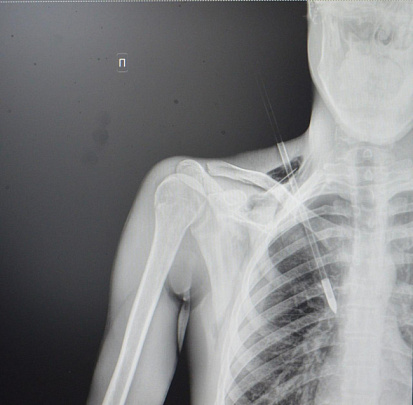

В Ступинскую больницу поступил 20-летний пациент с необычным ранением - стрелой в грудной клетке. Инцидент произошёл в парке, где молодой человек со своей девушкой занимались стрельбой из спортивного лука. По его словам, стрела рикошетом от дерева попала ему прямо в грудь.

Пациент был экстренно доставлен в операционную для удаления инородного тела. Стрела прошла между ключицей и первым ребром, пробив верхушку лёгкого на глубину около 6 сантиметров. К счастью, крупные кровеносные сосуды не пострадали.

"Пациенту невероятно повезло - стрела могла задеть подключичную артерию или вену, что привело бы к критическому кровотечению. Такие травмы требуют немедленного хирургического вмешательства. Мы успешно удалили инородное тело, а потом ушили поврежденное лёгкое и дренировали плевральную полость", - прокомментировал врач-хирург Ступинской больницы Тимур Колесников.